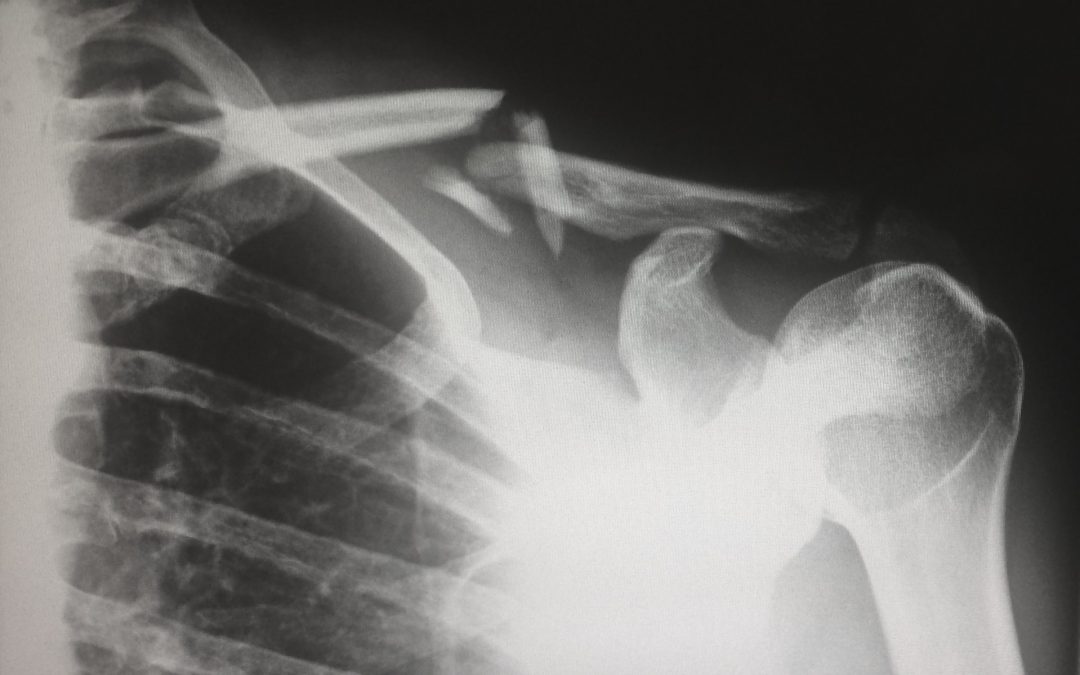

Dealing With a Broken Bone

The harder your children play, the harder they might fall. During childhood, fractures and broken bones are common for children playing or participating in sports. While falls are a common part of childhood, your pediatrician shares important information to help you...